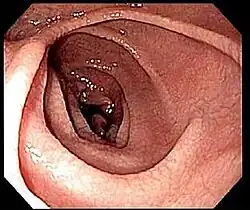

Na maior parte das pessoas com doença celíaca, o intestino delgado apresenta-se normal durante uma endoscopia. No entanto, existem cinco observações endoscópicas que sugerem doença celíaca: pregas mucosas serrilhadas, padrão em mosaico da mucosa (semelhante ao padrão de lama seca), proeminência dos vasos sanguíneos da submucosa e padrão nodular da mucosa.[67]